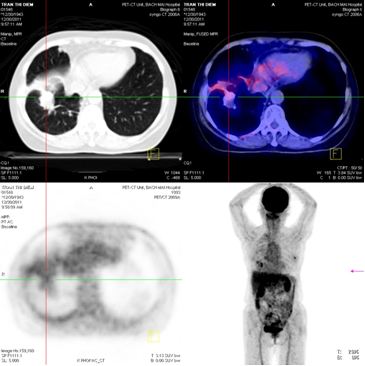

Chụp PET/CT:

Hình 4: Hình ảnh PET/CT có khối u thùy dưới phổi phải 2,6 × 2,8 cm, Max SUV= 5,32

Hình 5: Hình ảnh PET/CT có tổn thương cung sau xương sườn số 5 bên trái, và khối u não vùng đỉnh trái

Chụp PET/CT toàn thân sau 6 tháng điều trị:

Trước điều trị : Khối u thùy dưới phổi phải 2,6 × 2,8 cm, Max SUV = 5,32

Sau điều trị 6 tháng: U tan gần hoàn toàn

Hình 7: Hình ảnh PET/CT toàn thân sau 6 tháng điều trị: Khối u phổi tan hoàn toàn

Trước điều trị: tổn thương thùy đỉnh trái 2 cm

Sau điều trị 6 tháng: tổn thương tan hoàn toàn

Hình 8: Hình ảnh PET/CT toàn thân sau 6 tháng điều trị: Khối u não vùng đỉnh trái tan hoàn toàn.

Trước điều trị: Tổn thương cung sau xương sườn số 5 bên trái